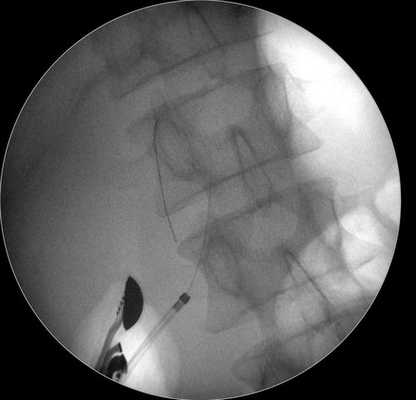

С помощью ультразвуковой навигации определяется безопасная траектория для внутреннего дренирования кисты. В инструментальный канал специального эхо-эндоскопа проводится цистотом, посредством которого формируется соустье между луковицей двенадцатиперстной кишки и просветом кисты (рис. 5 а, б).

Затем под контролем рентгеноскопии в полость кисты вводится струна-проводник для установки пластикового стента (double pigtail) диаметром 10 Fr и длиной 10 см. Осуществляется рентгенологический и ультразвуковой контроль: он подтвердил, что дистальный конец стента располагается в просвете кисты, проксимальный - в луковице двенадцатиперстной кишки (рис. 5 в, рис. 6). При эндоскопическом осмотре оценивается область сформированного соустья для исключения кровотечения (рис. 7).

Рис. 5 (в)